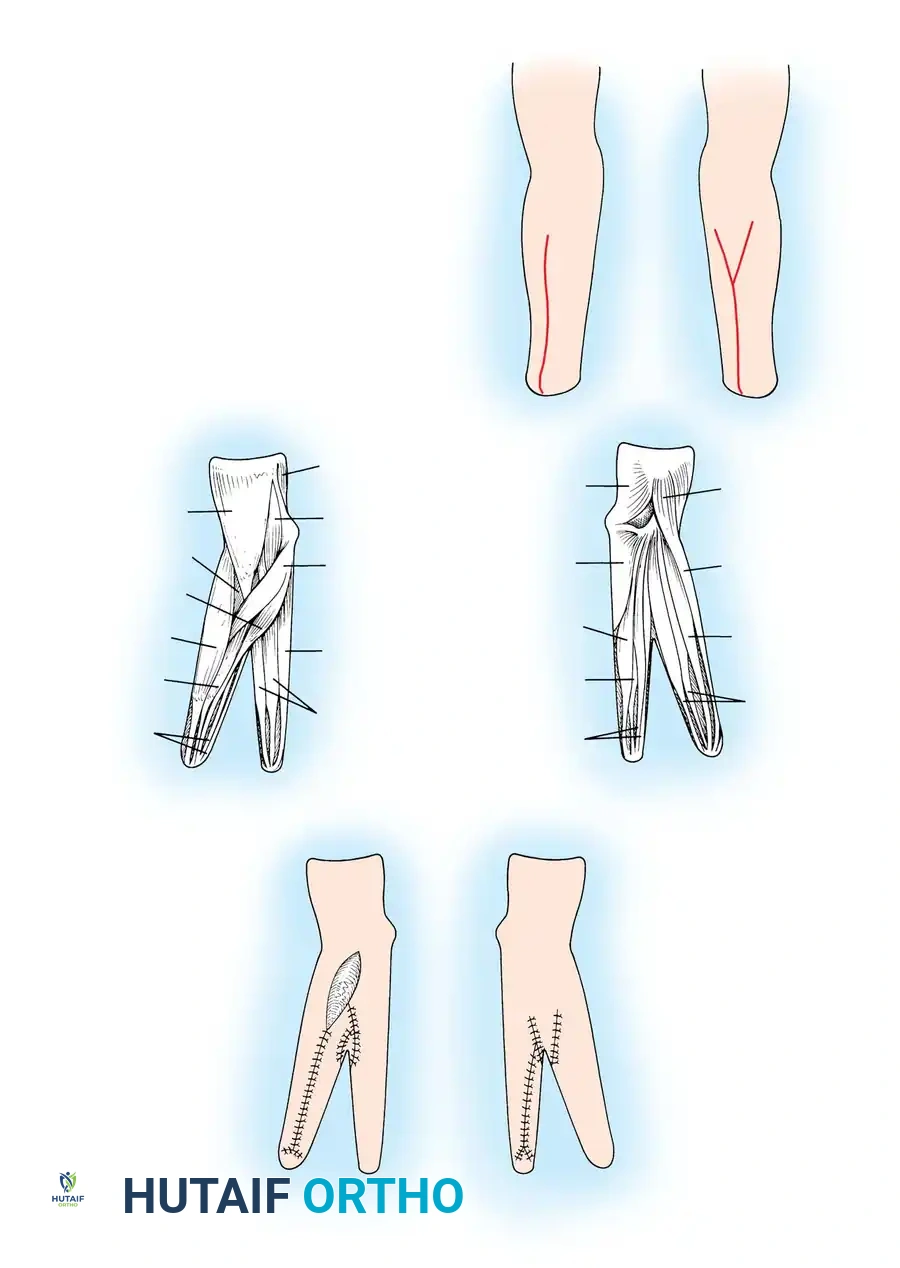

Fig. 76-3 A and B. Early fitting of a passive prosthesis in a child with a congenital forearm amputation is critical to encourage incorporation of the prosthesis into the child's body image.

1. 3 to 6 Months (Sit to Fit): A passive plastic mitten prosthesis is introduced once the child achieves independent sitting balance. This provides stability during sitting and assists in pulling to a stand.

2. 12 to 18 Months: The passive mitten is exchanged for an actively opened, plastisol-covered split hook. A Child Amputee Prosthetic Program (CAPP) terminal device may be substituted. Training with the functional device begins immediately.

3. 2 to 4 Years: A myoelectrical prosthesis may be considered. Studies have shown these to be highly useful and appropriate for preschool-aged children, offering superior cosmesis and intuitive grip control.

4. 3 Years and Older: For above-elbow amputations, dual-terminal devices and articulated elbow controls (friction elbows) are introduced.

Surgical Warning: Prosthetic management for midcarpal amputations remains controversial. The long, below-elbow stump is exceptionally useful for stabilizing objects and bimanual function because it retains native sensibility. Sacrificing terminal sensibility for a cosmetic artificial hand must be carefully weighed against the functional loss.